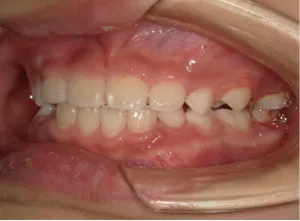

治療中③小2(7y8m):JUMP 受け口が改善

治療中④小2(8y2m)~小3(9y1m):QHとBHで拡大・アーチ形態の修正、ブラケットで前歯の並べ替えまで終了

| 行ったご提案・診断内容 | 成長期に行う治療と咬合治療をご提案 受け口用ファンクショナルアプライアンス(写真②③)からスタートし、小2以降で上下顎の拡大・歯列弓の形態修正・前歯の並べ直し(写真④)を行いその後、モノブロック(筋機能的咬合誘導)装置(写真⑤)へ移行し、受け口の再発予防と永久歯を適切な咬み合わせに誘導し、必要によりマルチブラケット法へ移行する治療方法を提案しました。 成長期治療(成長時期にお口の環境を整える治療) 2年生以降から 咬合治療 |

| 治療期間 | 12か月:受け口用ファンクショナルアプライアンス(写真②③) 12カ月:成長期治療の動的治療期間(写真④) 現在、成長の経過観察と咬合誘導中です(写真⑤~⑨) |